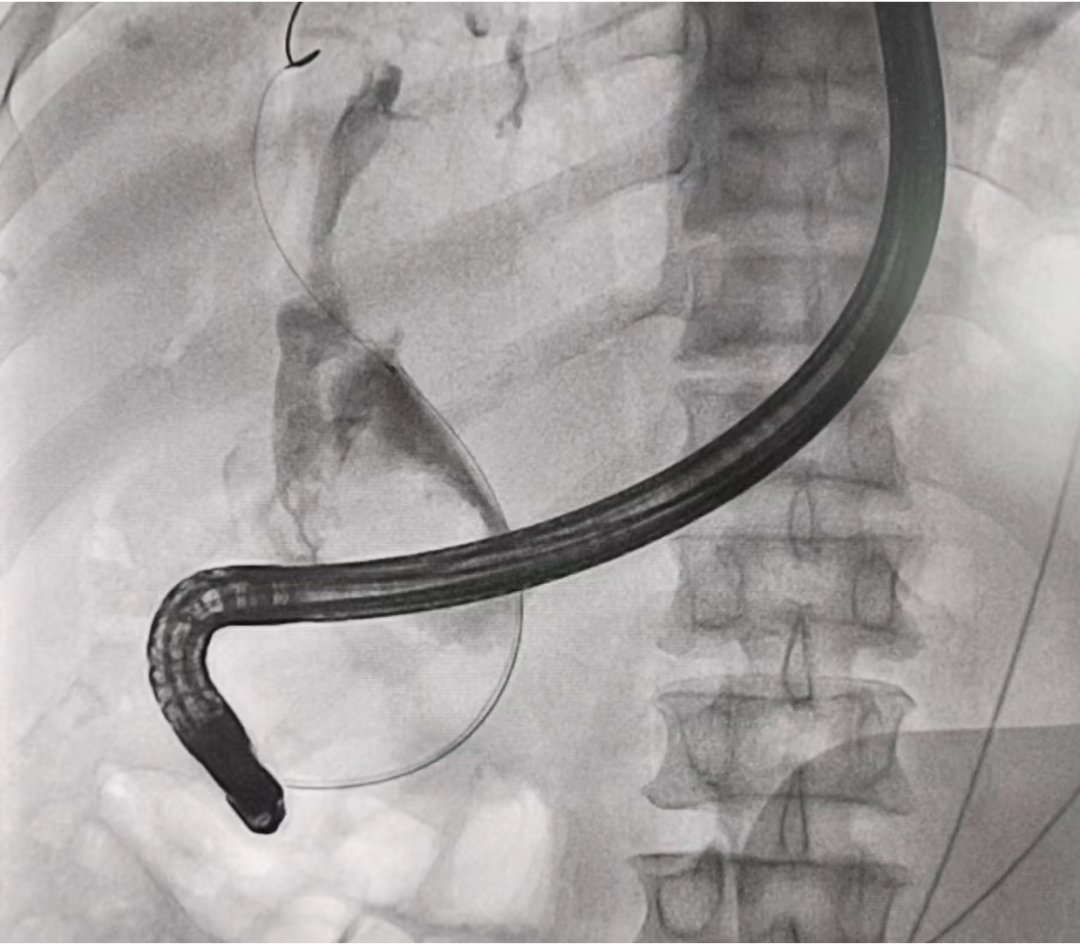

▲ 造影所见